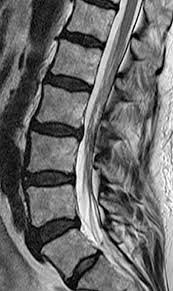

Tethered cord syndrome in adults indications. Tethered cord syndrome TCS is rare but no one knows exactly how prevalent it is because it commonly goes undiagnosed. Adult tethered cord is determined by an MRI which shows a low level of the conus medullaris below L2 and thickened filum terminale. Less qualifiers are acceptable with indirect imaging findings.

Indications techniques and long-term outcomes in. Adult tethered cord is determined by an MRI which shows a low level of the conus medullaris below L2 and thickened filum terminale. The occult tethered cord syndrome and surgical indication - PEDs Neuro Ortho UroGI Progressive Syringohydromelia Filum 2mm in axial section Derm ¾ clinical qualifiers mandatory for surgical indication. In adults symptoms are aggravated by trauma maneuvers associated with stretching of the spine flexion disc herniation and spinal stenosis. J Neurosurg Spine 42123-1312006. The tethering effect was caused either by a split cord malformation a thick filum terminale a conus medullaris lipoma with extradural extension or various combinations of these mechanisms. The authors performed a retrospective study of clinical outcomes after neurosurgical intervention in 60 adults with TCS. Of the 2515 patients 85 adults with a tethered cord syndrome formed the basis of this study. In the present study we analyzed the data of patients who presented with TCS in adulthood with the aim of studying the clinical spectrum and management strategies.